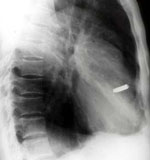

Negyven éven át élt puskagolyóval a szívében egy vietnami férfi, akit végül a múlt hét végén szabadítottak meg a háborús "emléktől" az egyik hanoi kórházban. A ma hatvanéves ember, a vietnami néphadsereg egykori katonája a vietnami háború során, 1968-ban

A háborús körülmények között azonnali, bonyolultabb műtétre nem volt lehetőség, a fiatal katona azonban mégis túlélte a súlyos sebesülést. Egy évvel később az orvosok megpróbálták eltávolítani a lövedéket, de kudarcot vallottak. A golyó pontosan az egyik szívbillentyűbe fúródott, s úgy helyezkedett el, hogy egy ideig nem veszélyeztette az egykori katona egészségét.

A férfi korosodásával azonban a lövedék mind gyakrabban panaszokat, majd végül infarktust okozott, s ez megkövetelte az újabb orvosi beavatkozást.

A hanoi szívkórház orvosainak ezúttal sikerült eltávolítaniuk a golyót, mégpedig a sérült szívbillentyűvel együtt, és azt mesterséges billentyűvel pótolták.